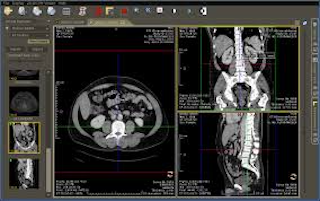

カルテ開示開示されたMRI画像をパソコンで見る

管理人は病院でMRI画像を撮影した際、CDやDVDで画像を貰っています。病院での医師の説明は極めて短く理解できませんので、自宅のパソコンで落ち着いて閲覧する目的ですが、必要な環境を整えないとスムーズには閲覧できないことがあります。

一般のパソコンはDICOM形式のファイルを閲覧するアプリケーションが添付されていません。そのため、何等かのアプリケーション(ビューア)が必要になりますが、病院からもらったCDやDVDにこのソフトも添付されている場合と添付されていない場合があります。また、病院によっては解像度は悪いですが、インターネット回線を使って「jpg」や「gif」や「png」画像を見れる方法も搭載しています。

CDにこの閲覧ソフトが添付されていない場合でも、ネット上からダウンロードしてみることが可能です。「DICOM viewer」や「DICOMアプリケーション」などと検索すれば、無料または有料のツールが多数公開されています。ただし、使用頻度が少ない個人が使うのには無料のアプリケーションで十分です。中には無料試供版と謳われているものもありますが、本製品は有料ですので注意してください。管理人は無料で使える「weasis」を使用しています。